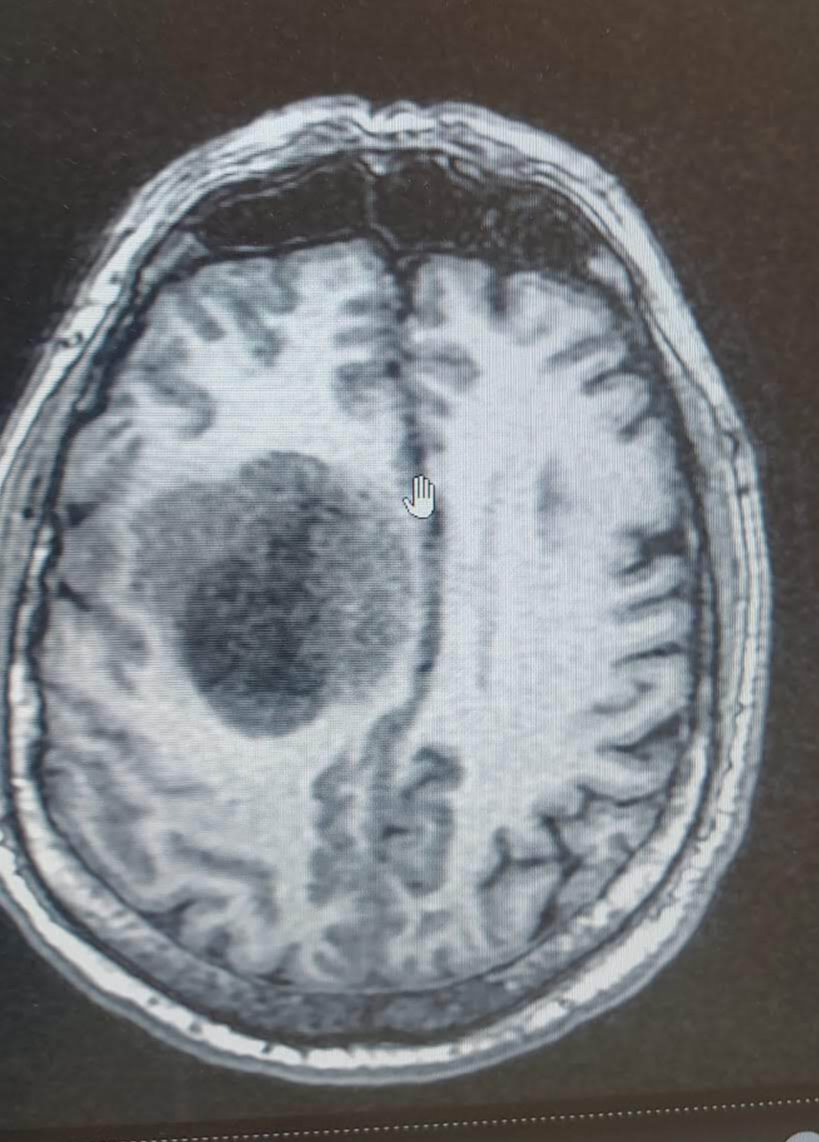

Отвечу тоже постом. Бывает даже и без Эпи приступов. Отец всегда был весёлым, активным, общительным человеком. А тут стали замечать, что "подвисает", будто не тут он, где-то в себе. Не такой болтливый. Мы с ним часами могли по телефону разговаривать, а тут звонит раз в день просто узнать как дела, только по делу, без болтовни. Думали может стареет, энцефалопатия. Где-то в июле- августе это началось. Когда потом врач его спрашивал про жалобы, отвечал: "жена сказала, что я изменился", то есть он не замечал ничего. Осенью за рулём на встречку его начало тащить. Потом вообще левая рука слушаться перестала. После того, как упал несколько раз за день, повезли в больницу. Там МРТ с контрастом: глиома IV, 5 на 5 см. Состояние буквально за два дня ухудшилось до такой степени, что перестал вставать (но сам он был в полной уверенности, что встаёт и ходит, видимо, мозг отказывался осознавать беспомощность тела). Причём, МРТ всего, и головы тоже, делали за полгода до этого. То есть болезнь развилась за считанные месяцы. Потом операция, химия, восстановление как после инсульта. Но прогнозы по этой болячке не слишком оптимистичные, он статистику не нарушил, к сожалению.

Вообще ничего не болело, больше никаких симптомов не было. Прислушивайтесь к себе и к близким. Иногда если что-то кажется, оно не кажется